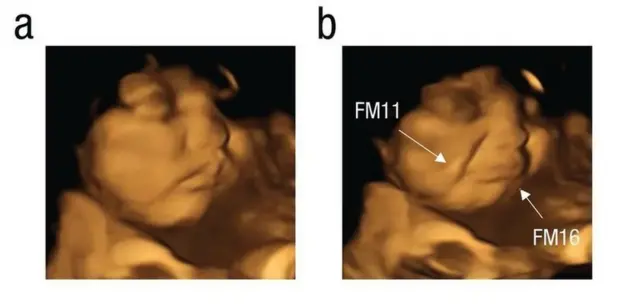

An nuna yanayin da 'yan tayin ke ciki ta hanyar na'urar daukar hoton ciki ta 4D

Masu binciken sun wallafa rahotonsu a mujallar kimiyya cewa minti 20 bayan da iyayen suka hadiyi kwayoyin, wata na'urar daukar hoton ciki mai suna 4D ta nuna yadda 'yan tayin - da ke cikin mahaifa da aka bai wa iyayensu kwayoyin da ke dauke da sinadarin ganye - na murtuke fuska (alamar rashin jin dadi).

Haka kuma na'urar ta nuna yadda 'yan tayin ke murmushi bayan da aka bai wa iyensu kwayoyin da ke dauke da sinadarin karas.

Su kuma matan da ba a bai wa komai ba jariran da ke cikinsu babu abin da suka yi.

Asalin hoton, Fetal and Neonatal Research Lab, Durham University